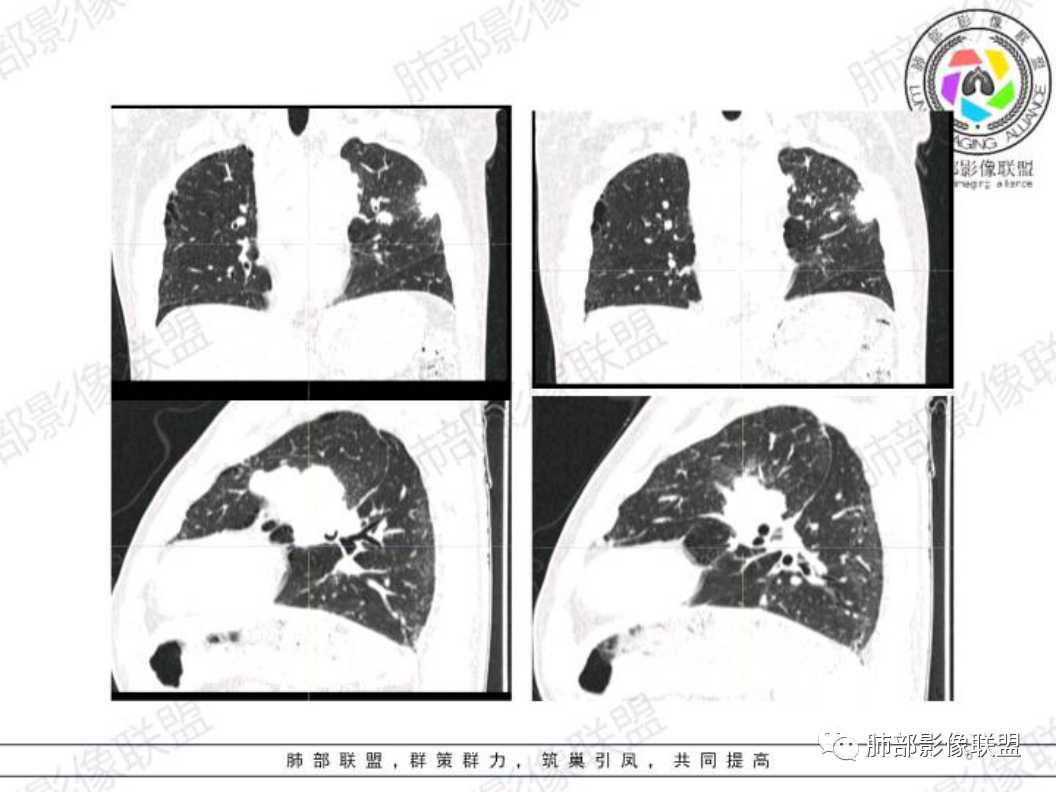

左肺上叶胸膜下实性结节,形态不规则,边缘毛糙,平行胸膜,近段支气管在病灶内堵塞,远端与胸壁相贴,左侧前纵隔多发肿大淋巴结融合,伴左肺门淋巴结肿大。

临床:中年男性,有糖尿病,考虑:小细胞肺癌?淋巴瘤?结核?建议完善增强检查,必要时穿刺检查。

中年男性患者,咳嗽、咳痰伴气喘加重3月,既往有糖尿病病史,肿瘤指标阴性,胸部CT:左肺上叶胸膜下斑片影,左肺门及纵隔淋巴结明显肿大并融合,考虑恶性,鳞癌,小细胞癌,鉴别结核。

左肺上叶胸膜下不规则结节影,平行胸膜长轴,毛刺,支气管进入截断,胸膜糊墙,纵隔多组淋巴结肿大融合,平扫部分淋巴结密度不均。考虑恶性,小。鉴别结核。

有糖尿病病史,左肺上叶胸膜下结节,边缘模糊,见长索条,临近胸膜糊墙,重建后结节饱满,边缘见短毛刺,纵隔见多发肿大淋巴结,融合并坏死,部分边缘可见点状钙化,首先考虑恶性,小细胞?腺癌?鉴别结核,建议增强检查或结合穿刺活检。

老年男性,糖尿病,CT左肺上叶胸膜下实性结节,有一定的膨胀性生长形态不规则,边缘毛糙,平行胸膜,左侧前纵隔及肺门多发肿大淋巴结融合,考虑恶性病变,小细胞癌或低分化腺癌伴转移可能。

中年男性,咳嗽咳痰一个月,有糖尿病史,肺纤维化病史,左肺门不规则肿块,边缘膨隆,有分叶,内有多灶性坏死,支气管截断阻塞,远端靠近胸膜下斑片实变影,纵隔淋巴结肿大,考虑恶性,小细胞肺癌可能性大,鉴别肺结核。

左肺上叶(上舌段)胸膜下斑块病灶,与胸膜界限不清,见栽赃浸润,形态不规则,左肺门和纵隔内多发肿大的淋巴结并部分融合成团块影,首选肺Ca,Nse高(考虑小细胞型)。